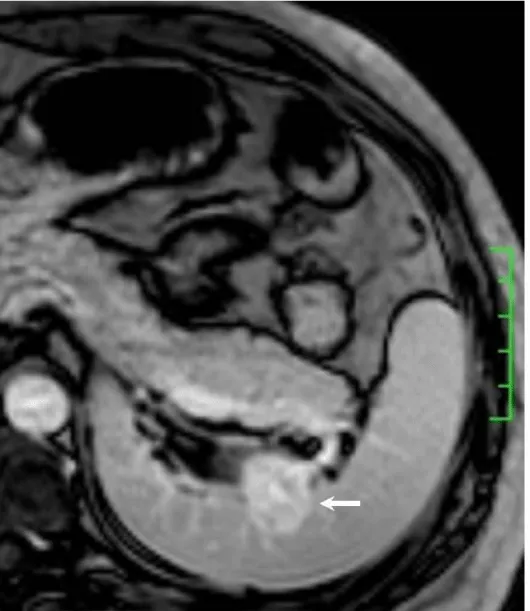

Solitary well-circumscribed masses were detected in all the five patients by ultrasound. One mass was of hypoecho, while the remaining masses were of hyperecho with posterior enhancement (Figure 1A). The maximum diameter ranged from 3.0 cm to 9.0 cm. At CT scanning, two masses appeared as hypodense (Figure 1B) and one was isodense (Figure 2A) to the normal spleenic parenchyma. In the two patients who received MR imaging, masses were isointensity at T1 weighted images (Figure 3A) and hypointensity with scattered sign void spots at T2 weighted images (Figure 3B). After intravenous injection of the contrast materials, all the five masses presented circle enhancement at arterial phase (Figure 3C and Figure 4A), while peripheral enhanced node was noted in one mass (Figure 2B). The circle enhancement persisted and radical line enhancement were observed at portal vein phase in 3 cases (Figure 1C) and progressive filling in was seen in two cases (Figure 2C). At delay phase of MR imaging, one lesion showed obvious enhancement with stellate low signal scar in the center comparing with surrounding splenic parenchyma (Figure 3D), while the other demonstrated central and circle enhancement to form a spoke-like appearance (Figure 4B). At delay enhanced CT scanning, two masses were isoattenuation to the surrounding splenic parenchyma (Figure 2D) and one lesion kept as hypoattenuation but with radial enhanced lines and enhanced circle to form a spoke-like appearance.

At pathological examination, all the masses were well demarcated on gross cut surface. A central stellate scar with peripheral interspersed dark brown nodules and the whitish intervening fibrous bands was noted to form spoke-like appearance (Figure 3E), which was well correlated with CT and MR imaging findings at enhancement. Microscopically, these angiomatoid nodules were surrounded by dense concentric collagen fibrous stroma and dispersed stromal cells with oval-to-spindle nuclei and scanty cytoplasm (Figure 3F). The abunden fibrous stroma may result in hypointensity at T2 weighted MR images. Hemosiderin was noted in the angiomatoid nodules (Figure 3G), which might contributed to signal void at T2 weighted MR images.

It usually affects middle-aged adults [6] and it is commonly found incidentally on radiographic imaging, or during operation for an unrelated condition. In present series, the patients are middle-aged adults without any related symptoms and the lesions were detected incidentally at routine ultrasound of health examinations. On ultrasound, manifestations of SANTs are vary widely from heterogeneous echo-texture with hyperechogenic, hypoechogenic, or isoechogenic appearing lesions, which are unspecific [7,8]. CT and MRI can show some characteristic features of SANTs, which include a solitary well demarcated mass with early peripheral enhancemant with radiating lines and progressive enhancement at the delay phase, and hypointens at T2 weighted MR images [2,3,5,9-13]. These features reflect the underlying pathological changes of scattered angiomatoid nodules separated and surrounded by sclerotic fibrotic stroma [10]. In present series, we also observed these characteristic features with well correlation to pathological findings. Circle and spoke-like enhancement can be contributed to fibrotic stroma surrounding and separating the angiomatoid nodules. The sclerotic fibrotic stroma may also result in isodense on CT, isointensity on T1 weighted images and hypointensity on T2 weighted images of MR imaging. The signal void spots at T2 weighted MR images have not been described at other literatures and may be contributed to hemosiderin deposition due to magnetic susceptibilty artifact.